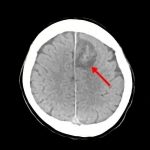

断層撮影